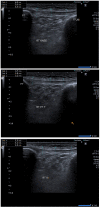

Methods: This parallel group, single-blinded randomized controlled trial was carried out involving 94 athletes with clinically diagnosed jumper's knee, divided into an intervention group (USG-DN + CPT, n = 47) and a control group (CPT, n = 47). Participants received a 4-week programme; the intervention group received ultrasound guided patellar tendon dry needling (DN) in conjunction with CPT. The control group received only CPT. The visual analog scale (VAS), Victorian institute of sports assessment-Patellar tendinopathy (VISA-P) questionnaire, Lysholm scale, Knee injury and osteoarthritis outcome score (KOOS) and ultrasonographic features of patellar tendinopathy were evaluated at baseline,1 week, 2 weeks, and 4 weeks. The data were analyzed through SPSS-26.

Results: The study found statistically significant differences (P < 0.05) regarding VAS, Lysholm, VISA-P, and KOOS scales at baseline, 1st, 2nd, and 4th week post-intervention. Within-group differences also showed statistically significant results after the intervention. There were significant results observed in ultrasonographic outcomes between both groups at 1 month post-intervention (all P < 0.05).

Conclusion: The results of the current study suggest, ultrasound guided DN of patellar tendon in combination with CPT reduced pain, improved function, and showed a tendency to decrease tendon thickness in patients with patellar tendinopathy.